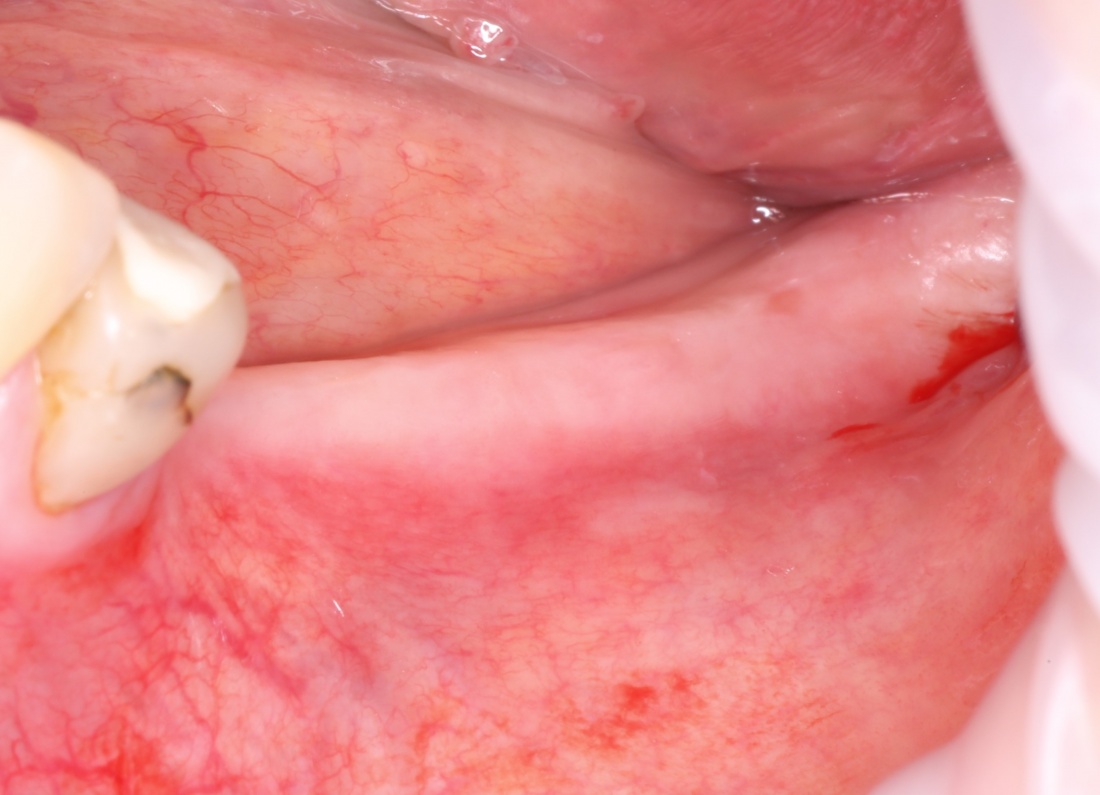

Если на этапе разреза и формирования раны всё сделано правильно, то наложение швов не вызывает особых трудностей. Периостотомия или послабляющие разрезы на периосте не требуются (ни практически никогда не требуются). А сами швы получаются аккуратными и герметичными:

Обрати внимание, что все шовные лигатуры находятся в пределах кератинизированной десны. Это позволяет избежать деформации тканей и лишних рубцов. В наиболее уязвимых местах (около зубов) шовные лигатуры лучше продублировать.

Если бы мне пришлось делать это сейчас, то я бы использовал непрерывный «матрацный» шов. Он удобнее, быстрее в наложении и комфортнее для пациента. Минус — если распускается, то распускается весь. К тому же, его очень неудобно снимать.

Несмотря на то, что уже тогда мы широко использовали непрерывные швы в подобных случаях, здесь я, во-первых, зассал (может распуститься), во-вторых, снятие швов предполагалось в поликлинике по месту жительства пациентки, и мне не хотелось, чтобы там при снятии швов начудили. Как выяснится позже — зря беспокоился.

Неизменно одно — в таких операциях мы использовали и до сих пор используем нерезорбируемые монофиламентные шовные материалы, поскольку они наиболее гигиеничные. Чтобы острые концы нитей не беспокоили пациента, их можно оплавить нагретой гладилкой или гуттаперчевым плаггером.